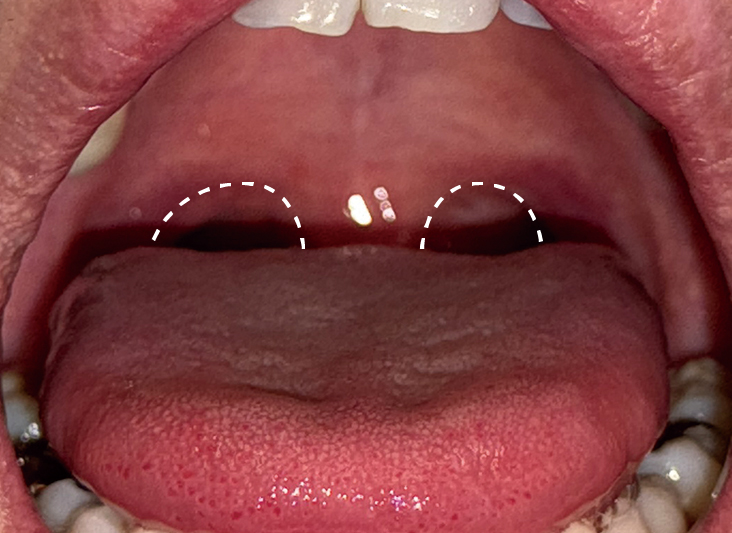

いびきレーザー治療の症例写真

Before

After(1回目)